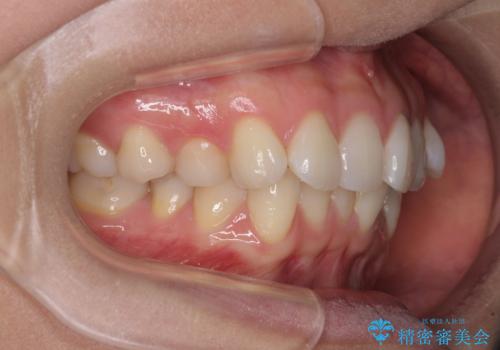

前歯のデコボコを解消 インビザラインの矯正治療

- 前歯のデコボコを治したいとのことで来院された患者様です。

上下顎ともに歯列全体の後方移動とIPR(歯と歯の間を削る)によってデコボコが解消するように設計し、インビザラインにより治療を行うこととしました。